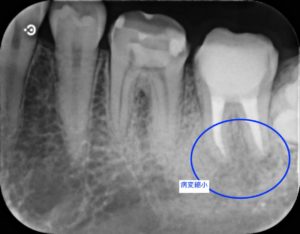

治療前

根管治療終了直後

根管治療終了後3ヶ月

根管治療終了後1年

左下第二大臼歯部に不良補綴物をみとめたため、レントゲン検査を行うと根尖部透過像がみられた。根管内に破折器具がみられたため、破折器具の除去および根管内の感染除去を行った。経過観察後、根尖部透過像の縮小をみとめたため、歯冠修復を行った。

今回の症例では根管内の汚染が強く、破折器具もはじめからしっかり見えたことから超音波切削器具と次亜塩素酸ナトリウム等を用いて除去しました。再度根管充填を行ったあと、病変の縮小をみとめた後に歯冠修復を行いました。

大きな根尖病変の存在する歯であっても保存可能な場合もありますので、お悩みの方はぜひご相談ください。